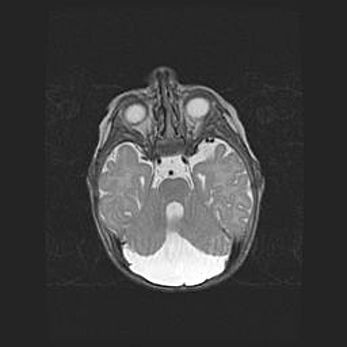

Аномалия Денди-Уокера. Признаки гипоплазии мозолистого тела.

Возраст: 5 месяцев 3 дня

Вес: 5550 г

Пол: мужской

Окружность головы: 39 см

Срок гестации: 40 недель

Аномалия Денди-Уокера – это порок развития головного мозга, для которого характерна триада симптомов: гипотрофия или аплазия червя мозжечка и/или полушарий мозжечка, расширение четвёртого желудочка с формированием ликворной кисты задней черепной ямки, гипертензионная гидроцефалия различной степени.

Гипоплазия мозолистого тела относится к дефектам внутриутробного этапа развития мозговой ткани, возникающим в процессе закладки структур головного мозга, что происходит на начальных этапах развития эмбриона.